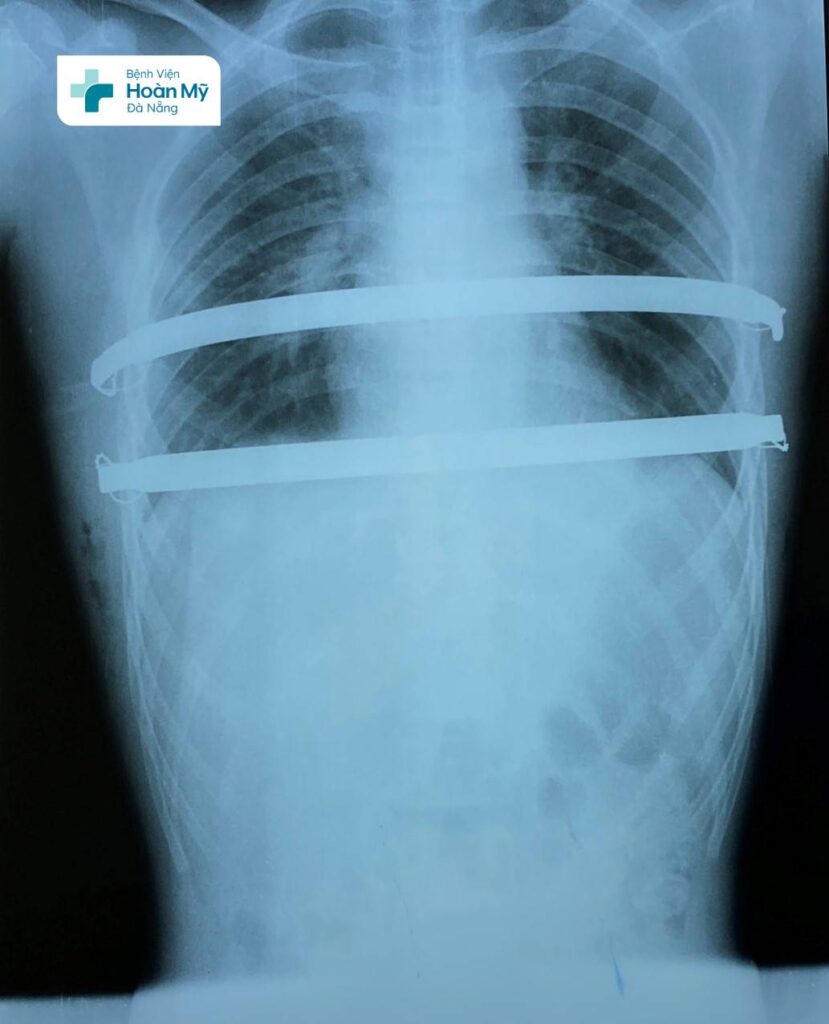

ThS.BS Nguyễn Thanh Hiền – Trưởng khoa Ngoại Tim mạch, BV Hoàn Mỹ Đà Nẵng cho biết: “Những năm gần đây, Khoa Ngoại Tim mạch đã phẫu thuật điều trị lõm ngực hiệu quả, cải thiện tính thẩm mỹ cho nhiều người bệnh, bao gồm cả trẻ em và người lớn. Trước đây với phương pháp phẫu thuật cũ, bác sĩ sẽ thực hiện một vết mổ lớn ở khu vực giữa ngực để tách sụn trước, đặt thanh nâng kim loại, người bệnh lo ngại việc để lại sẹo xấu. Hiện nay, với phương pháp NUSS, bác sĩ chỉ rạch 2 đường rất nhỏ 2 bên ngực người bệnh, đặt thanh nâng xương ức bằng titan đã được uốn cong vào lồng ngực (trước tim, sau xương ức) đảm bảo thẩm mỹ & giảm nguy cơ chảy máu, nhiễm trùng. Đây là phương pháp phẫu thuật xâm lấn tối thiểu với ưu điểm về thời gian phục hồi nhanh, có thể rút thanh nâng sau 2 năm đặt chỉnh hình lồng ngực.”

Thanh nâng xương ức bằng titan đã được uốn cong vào lồng ngực (trước tim, sau xương ức) đảm bảo thẩm mỹ